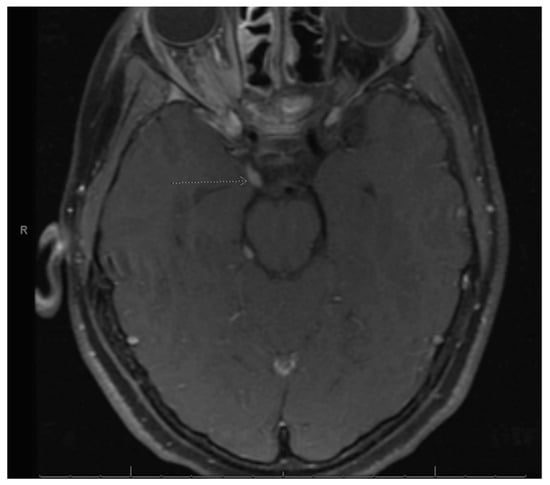

Our patient is a Hispanic female who first presented at age 2 with clumsiness and dysarthria. Her initial MRI brain/face revealed right vestibular schwannoma but no other NF2-related pathology. Genetic testing was sent from a serum blood sample to the University of Alabama and analyzed for next generation sequencing (NGS) as well as duplication/deletions using multiplex polymerase chain reaction (PCR) assay (MLPA). It revealed a specific pathogenic mutation, c.-854-??46+??deletion, which was previously identified in her father who was diagnosed with NF2. There was no biallelic loss of NF2. Shortly thereafter, she underwent removal of a forehead lesion with pathology confirming a schwannoma. At age 4, a 7-mm enhancing lesion filling the right L1-L2 neural foramen was identified and thought to be a nerve root schwannoma. At age 5, brain MRI revealed a growing right optic nerve/optic nerve sheath that appears slightly fuller in the orbital apex, with concerning meningioma (Figure 1). Since she was not a surgical candidate, she received proton beam radiation therapy to the right optic nerve meningioma and a right cranial nerve schwannoma with a total of 48.6 cGy in 27 fractions without any systemic therapy. At age 8, she was noted to have mild to moderate conductive hearing loss for the right ear, normal hearing sensitivity for the left ear and right middle ear disorder. At age 11, she was noted to have hypothyroidism and started on levothyroxine. She was also being treated for attention deficit hyperactivity disorder (ADHD), anxiety, depression and self-harming behavior.

Figure 1. Right optic nerve sheath tumor. Arrow is pointing to the right optic nerve sheath tumor as stated in the figure title.